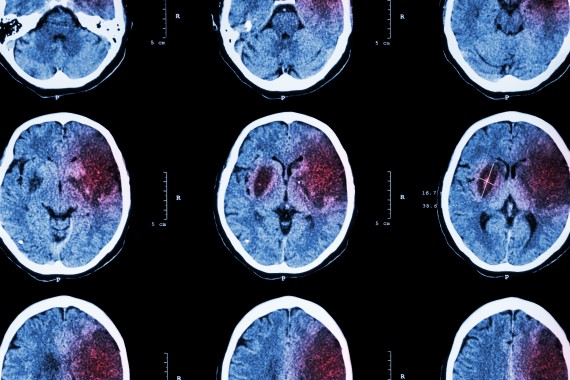

The usual treatment for a stroke caused by a blood clot in the brain (ischaemic stroke) is to give patients clot busting therapy - if the ‘clot buster’ drug can be given within 4.5 hours of the onset of symptoms (a crucial time window where the benefits of treatment have been shown to outweigh risks, such as bleeding). But what should doctors do if patients don’t know when they’ve had a stroke? This happens frequently in ‘wake-up stroke’, where people have a stroke while they are sleeping and then wake up with symptoms. It often isn’t known when exactly symptoms developed, and these patients are usually not offered clot busting therapy.

The results of recent trials have suggested that clot busting treatment might benefit people with wake-up stroke, specifically when specialised imaging scans can pin point that the stroke has probably taken place within 4.5 hours of waking, or that the part of the brain affected by the stroke is not irreversibly damaged. But the sophisticated type of imaging used in these clinical trials is not available to all patients.

The international Tenecteplase in Wake-up Ischaemic Stroke Trial (TWIST) was designed to find out if routine imaging with a simple CT scan (used in everyday practice) could identify patients with wake-up stroke who might benefit from clot busting therapy.

All patients then had a CT scan to see if they were eligible to enter the trial. They were excluded from participating in TWIST if the CT scan showed a bleed in the brain (where clot busting treatment is contraindicated), if the area of brain damaged by the stroke was very large, or if their symptoms were very severe – instances where it’s known that clot-busting treatment is unlikely to be beneficial, and therefore the risks of treatment outweigh the potential benefits.